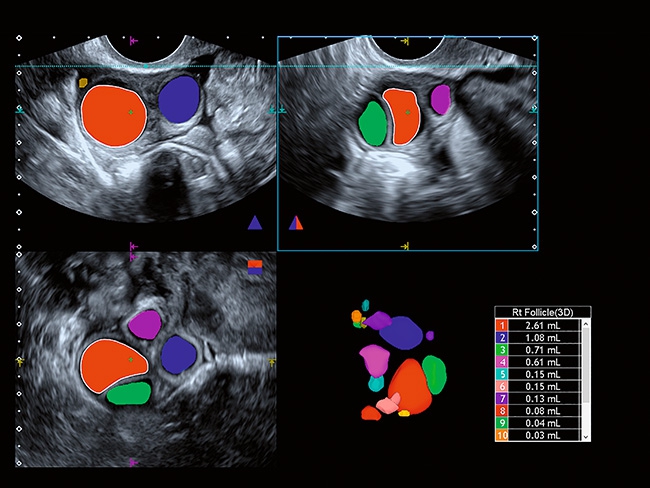

Aplio a550 может работать с линейным матричным датчиком и поддерживает новейшие монокристаллические датчики. Также Aplio a550 поддерживает большое количество дополнительных опций, таких как - SMI, Компрессионная эластография, Эластография сдвижной волны, Smart Fusion, исследования с использованием контраста (CEUS), 3D реконструкции в реальном времени (4D), функции автоматической оценки подвижности миокарда и фракции выброса.

Отличная цветопередача с высокой детализацией и четкостью изображения. Устройство подходит для профессионального использования в частных кабинетах и крупных медицинских центрах. Комплектация сканера применима для самых разных исследований. Широкий диапазон прикладного клинического программного обеспечения высокоэффективен для общих исследований, сердечно-сосудистых, гинекологических, ортопедических, урологических.